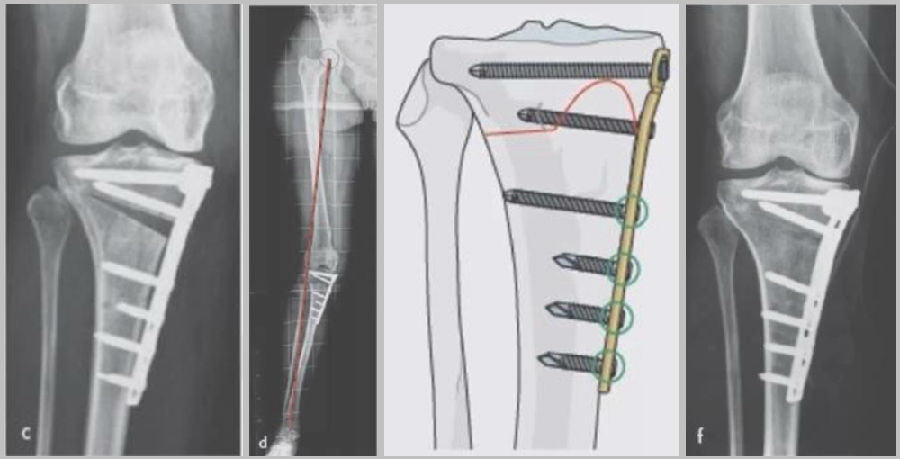

(2)Ⅱ型骨折

当出现Ⅱ型骨折时要特别注意,因为此时截骨的远端就是骨折的远端,近端只有上胫腓周围骨筋膜存在,所以相对来说Ⅱ型骨折并不稳定。

首先用拉力螺钉复位,调整好力线。然后做结构性植骨,延迟负重,所谓延迟负重就是延迟到外侧合页和上行截骨线处达到初始愈合,然后再让患者进行负重。如果不做结构植骨加延迟负重,就会出现一些非常严重的现象,如不愈合。

拉力钉复位,结构性植骨

左侧患者未植骨正常负重,术后4个月不愈合;右侧患者非结构性植骨过早负重,术后1年未愈合

(3)Ⅲ型骨折

首先要把截骨撑开钳拿下来,此时骨折端会自动复位,然后再由外向内侧打入一颗拉力螺钉,将胫骨平台做临时固定,然后再进一步的用摆锯锯或是用骨刀打,保留1cm的合页,最后再进行撑开,做内固定。同样要求患者做结构植骨加延迟负重。

截骨偏前,截骨线过短;Ⅲ型骨折;保留1cm合页

结构植骨,外侧拉力钉固定